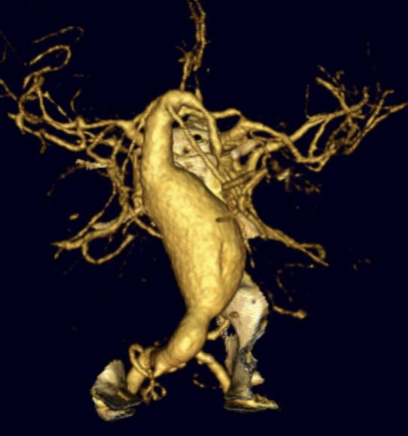

Intracranial Aneurysms

• Intracranial aneurysms are abnormal dilations of cerebral arteries that can rupture and cause life-threatening subarachnoid hemorrhage. Their formation is influenced by genetic, hemodynamic, somatic mutations and inflammatory factors that weaken the vessel wall over time. Research in this field seeks to uncover the molecular mechanisms of aneurysm initiation, growth, and rupture, develop predictive biomarkers, and refine surgical and endovascular treatments to prevent bleeding and improve patient outcomes.